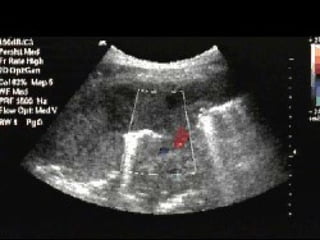

PROCEDURE Landmarks Aproach #2 –Anterior Mid-Axillary View 1 Place probe longitudinally in right anterior mid-axillary line with marker towards the head 2 Look for IVC running longitudinally adjacent to liver crossing the diaphragm. 3 Track superiorly until it enters right atrium confirming that it is the IVC and not the aorta.

• 138.

Measuring the IVCDiameter Measure IVC 2cm